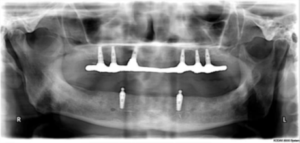

The dentist first performs a comprehensive examination, including digital X-rays, CBCT scans, and oral evaluation. This helps determine bone density, jaw structure, and suitability for the All-on-Four procedure.

Based on the diagnostic results, a customized treatment plan is prepared. The dentist determines the optimal position and angle for placing the four implants.

During the procedure, four titanium dental implants are surgically placed into the jawbone. Two implants are placed vertically at the front of the jaw, while the other two are angled toward the back to provide maximum stability.